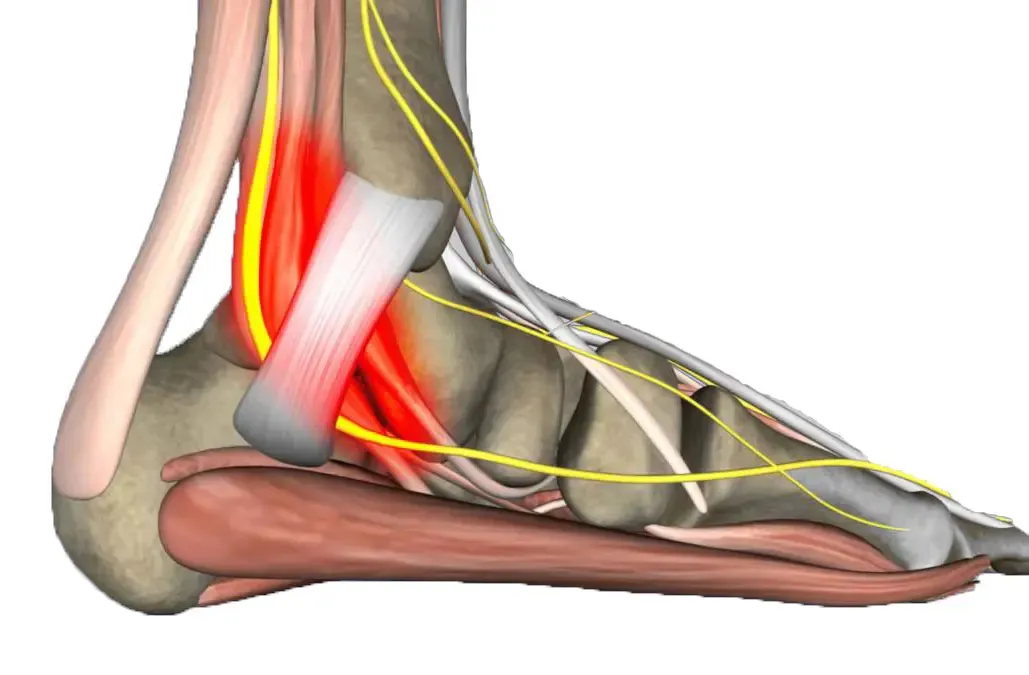

El dolor de talón es la consulta más frecuente en podología, y en la mayoría de los casos tiene un componente biomecánico que es fundamental abordar para lograr una solución duradera. Las plantillas personalizadas corrigen las alteraciones en el apoyo del pie que sobrecargan la fascia plantar y las estructuras del talón.

Las plantillas son más eficaces cuando se combinan con otras terapias que aborden la fase aguda del dolor. En nuestro centro las integramos con ondas de choque, electrólisis percutánea o terapia láser según las necesidades de cada paciente, logrando un abordaje integral del dolor de talón.

Espolón Calcáneo

Dolor intenso en el talón al pisar, especialmente por las mañanas.